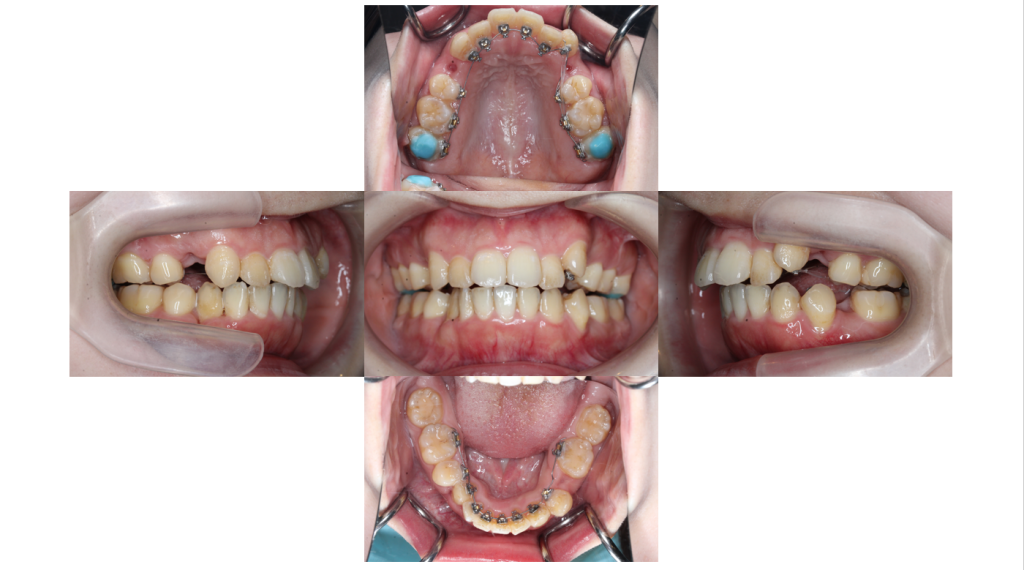

叢生・裏側矯正の症例上下装置装着後の口腔内写真です。

2ヶ月経過

叢生・裏側矯正の症例2ヶ月経過し、内側に入り込んでいた歯も並んできました。

3ヶ月経過

叢生・裏側矯正の症例小さな仮の装置がついていた左上犬歯も動いてきました。

6ヶ月経過

叢生・裏側矯正の症例治療開始から約6ヶ月が経過し徐々に歯列がアーチに近づいてきました。

主訴 上の前歯のでこぼこ、前歯の後ろに歯が生えている

抜歯 有(4┴4、4┬5)

矯正の装置 裏側矯正(舌側矯正)